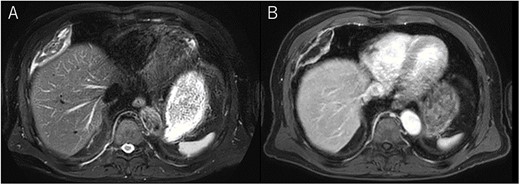

A 72-year-old man with a history of hypertension and left renal cancer (Stage I) was referred to us with a mass in the right chest wall on post-operative follow-up chest computed tomography (CT) for renal cancer. He had a smoking history of 20 pack-years and had no exposure to environmental fumes or dust. Physical examination results were unremarkable. The laboratory findings were within normal limits. Pulmonary function tests and cardiovascular examinations revealed normal results. Chest CT revealed mixed density mass (8.0 × 5.0 × 3.0 cm) located in front of thoracic wall in the third to sixth right intercostal space. The tumor can be revealed as thoracic wall fat (7.8 × 4.8 × 1.2 cm) on CT 1 year before (not considered as abnormal), and it was progressively increased in size and the density changed (Fig. 1A and B). Magnetic resonance imaging (MRI) showed a fatty mass of heterogenic density. T2 high foci (Fig. 2A) and irregular marginal enhancement of the tumor were observed (Fig. 2B). Maximal standard uptake value (SUVmax) of 18F-fluorodeoxyglucose positron emission tomography (FDG-PET) was 3.78 (Fig. 3). Based on these radiological image findings, we scheduled surgery with suspicion of liposarcoma. During the surgery, the patient was placed in the lateral decubitus position. We made 1.5-cm incision in the sixth intercostal space along the posterior axial line for thoracoscopy. We found dense adhesions between the chest wall tumor, lung (front part of all three lobes of the right lung) and diaphragm. We made a 30-cm incision in the fourth intercostal space and resected the tumor along with lung (wedge resection of the front part of all three lobes of the right lung), diaphragm and third to sixth ribs and intercostal muscle. The chest wall defect was 25 × 15 cm and the diaphragm defect was 8 × 5 cm. For reconstruction, the mesh was placed and sutured to the diaphragm and the chest wall. Pathological examination revealed the well-circumscribed tumor with fibrous adhesion between the ribs, lung and diaphragm (Fig. 4A). Microscopically, the tumor consisted of mature fat tissue. There were fat necrosis inflammatory changes in the marginal area of the tumor with foamy macrophages and multinucleated giant cells (Fig. 4B and C). Fluorescence in situ hybridization examination for murine double-minute 2 was negative. Based on these findings, a chest wall lipoma was diagnosed. The post-operative course was uneventful. The patient was followed up for 24 months without evidence of recurrence.

Mixed density mass located in front of thoracic wall; the size was 8.0 × 5.0 × 3.0 cm (B); (A) The tumor seen as thoracic wall fat (7.8 × 4.8 × 1.2 cm) (arrow) on CT 1 year ago; (B) the size increased and the density has changed to heterogenous in 1 year.